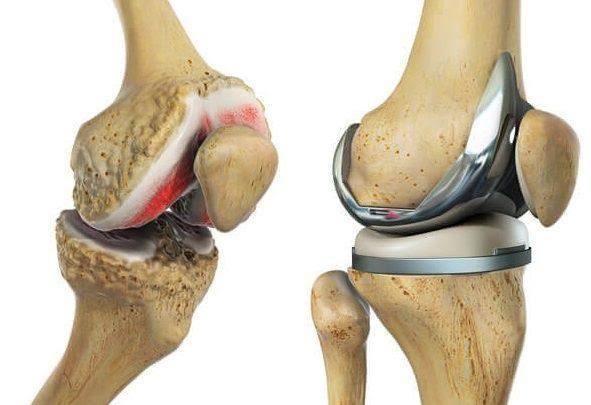

A total knee replacement (TKR) is a surgical procedure that resurfaces damaged knee joint surfaces with metal and plastic components to relieve severe pain and disability, most commonly caused by arthritis. It is typically recommended when other treatments fail to provide adequate relief.

The procedure involves removing damaged bone and cartilage from the thigh bone (femur), shin bone (tibia), and sometimes the kneecap (patella), and replacing them with artificial components. Recovery includes structured physical therapy to restore mobility and strength.

- Resurfacing: The surgeon reshapes the ends of the femur and tibia and resurfaces the underside of the patella using durable metal and plastic implants.

- Components: The artificial knee typically includes a metal femoral component, a metal tibial plate, and a plastic spacer between them, often with a plastic “button” for the kneecap.